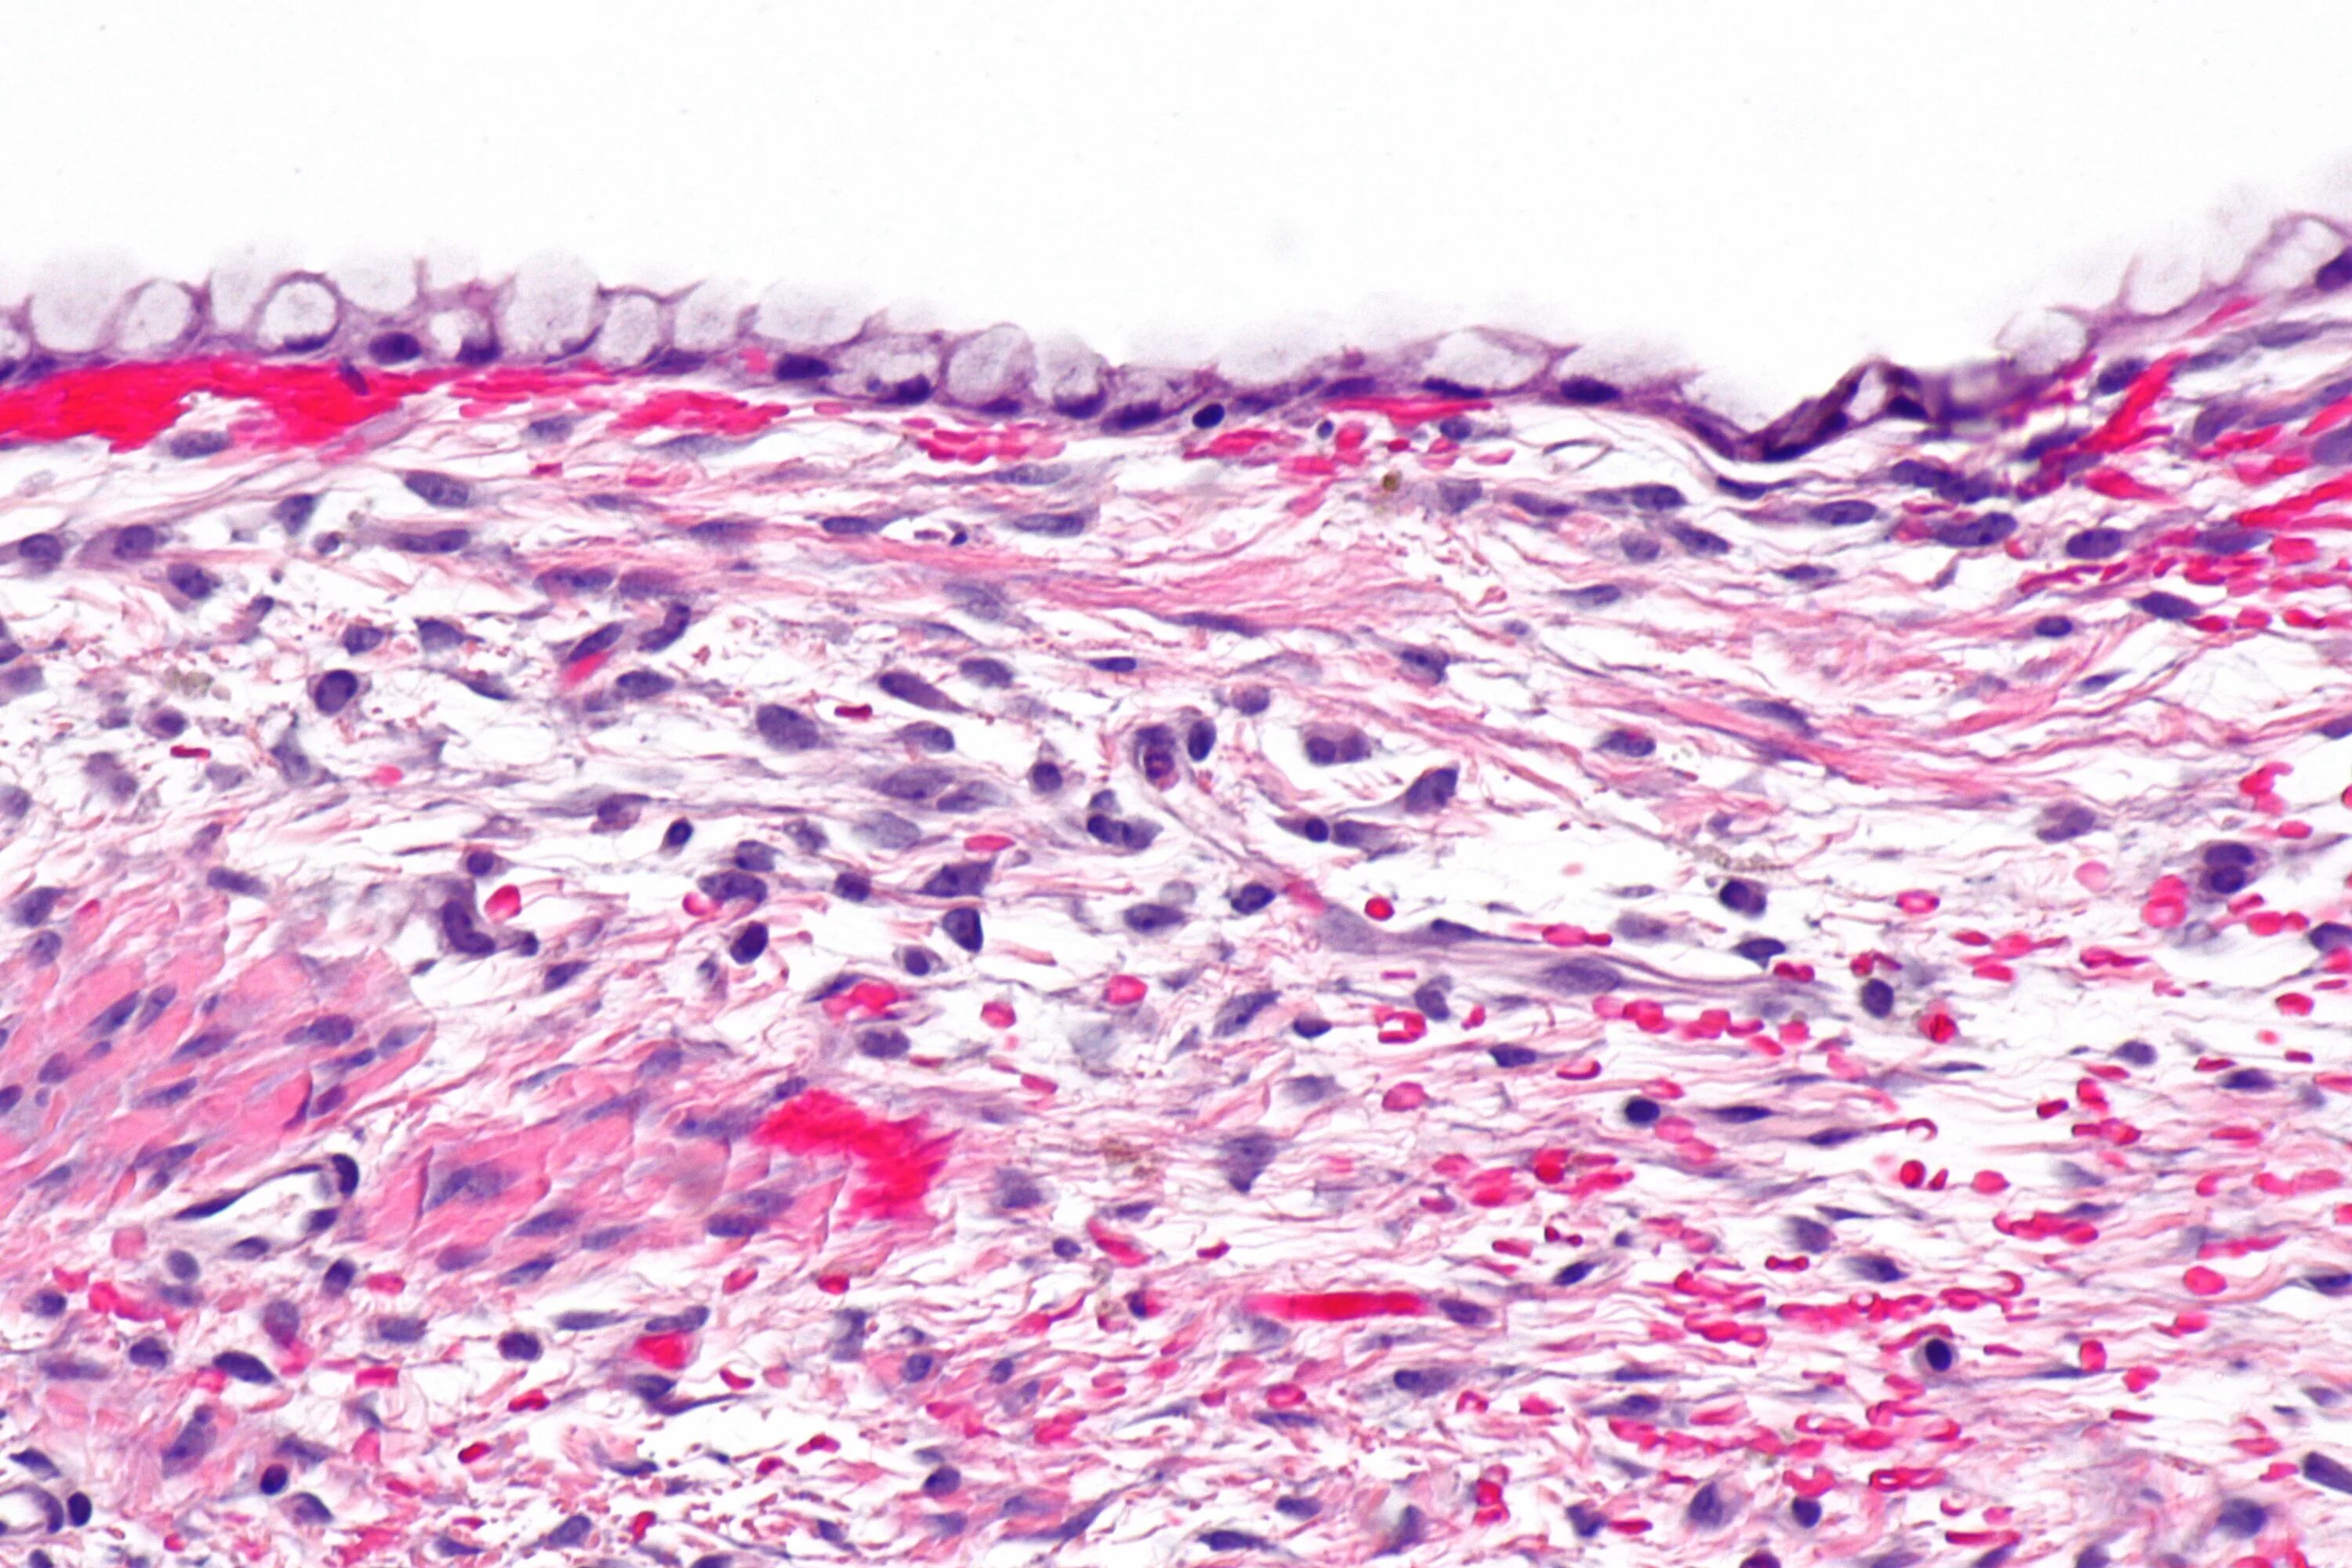

Гистология цистаденомы